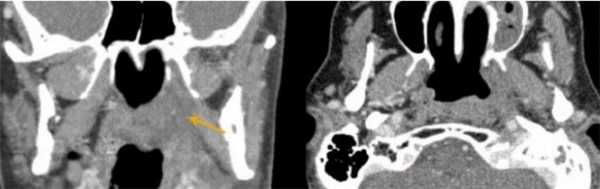

КТ носовых пазух (фронтальный срез). Стрелками отмечено утолщение слизистых оболочек

Снимки МСКТ показывают контуры, структуру, плотность всех частей пазух. По фото врач может произвести оценку:

расположения носовой перегородки;

путей дренирования синусов;

симметричности сторон носа и пазух;

степени пневматизации придаточных полостей;

состояния слезных протоков.

КТ дает изображения в поперечной (аксиальной) проекции. В специальной программе фото можно увеличить и рассмотреть мельчайшие детали. При помощи реформатирования рентгенолог реконструирует картинку в желаемой анатомической плоскости. Чаще всего это две дополнительные проекции - корональная (фронтальная) и сагиттальная (делит объект на левую и правую части). Также есть возможность создать объемную модель, отрезать «лишние» фрагменты, что упрощает изучение области интереса и облегчает трактовку данных.